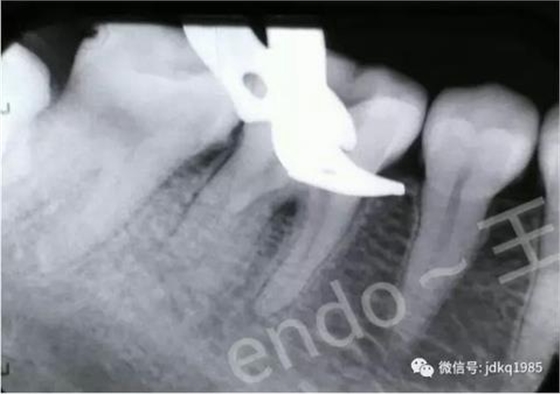

術(shù)后X線片,確認(rèn)近中根管內(nèi)分離器械已成功清理